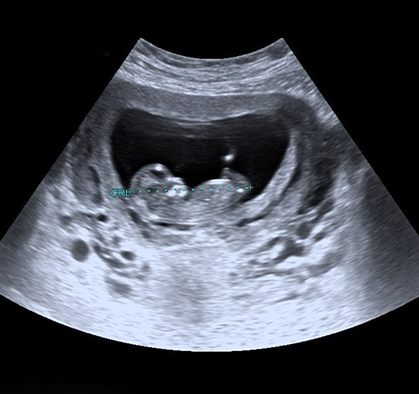

정밀 초음파 검사

임신 기간 동안 태아의 성장과 건강 상태를 확인하기 위해 정밀 초음파 검사가 진행될 수 있습니다.

초기 정밀 초음파 (11주 ~ 13주)

태아 목 뒤 투명대 두께를 측정하여 염색체 이상 가능성을 확인하는 검사입니다.

중기 정밀 초음파 (21주 ~ 24주)

태아 주요 장기 구조를 확인하여 기형 여부를 확인하는 검사입니다.

입체 초음파 (27주 ~ 28주)

태아의 외형을 입체적으로 확인하는 4D 초음파 검사입니다.